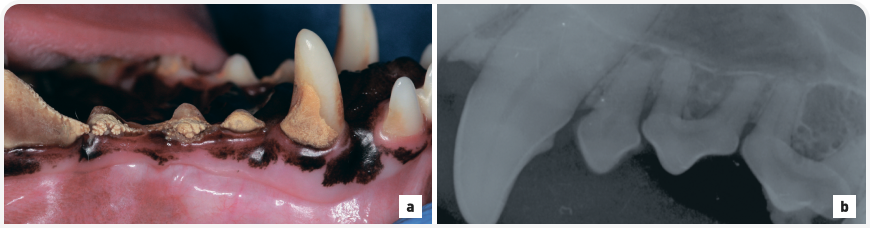

Собаки мелких пород предрасположены к переломам нижней челюсти. Переломы могут быть травматическими, патологическими или ятрогенными. Травматические переломы возникают в результате дорожно-транспортных происшествий или укусов других (более крупных) собак. Наиболее частой причиной патологического перелома у собак мелких пород является тяжелый хронический пародонтит (Рис. 8). У собак мелких пород также повышен риск ятрогенного перелома, например вследствие избыточного применения силы при удалении зубов.

Рисунок 8. Мопс в возрасте 6 лет поступил с предполагаемой болью во рту, наблюдавшейся в течение 2 месяцев. (a) Внутриротовая рентгенография зубов (визуализация левых премоляров нижней челюсти, техника деления угла пополам) показала полный поперечный патологический несращенный перелом нижней челюсти через лунку дистального корня нижнего левого третьего премоляра и мезиальный корень нижнего левого четвертого премоляра. Премоляры скучены, наблюдается полная потеря прикрепления корней на линии перелома. Перелом предположительно вызван тяжелым пародонтитом, вероятно, ускоренным в результате скучивания и поворота этих зубов. (b) Трехмерная реконструкция с помощью конусно-лучевой компьютерной томографии позволила получить более подробную информацию о переломе (стрелка). (c) После хирургического удаления третьего и четвертого левого премоляра нижней челюсти для стабилизации перелома во время его сращивания была установлена модифицированная межзубная проволока Рисдона и проведено шинирование композитным материалом. Фотография была получена в дорсальном лежачем положении пациента.